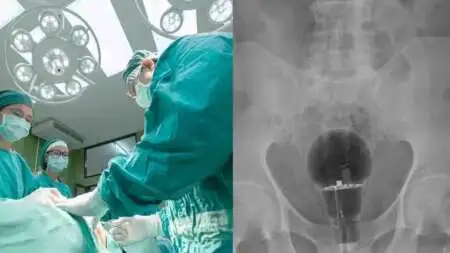

Άναυδοι έμειναν οι γιατροί σε νοσοκομείο της Κολομβίας, όταν διαπίστωσαν πως μια λάμπα βρισκόταν μέσα στον πρωκτό ενός ασθενή, 53 ετών.

Ο ασθενής, ο οποίος δεν έχει κατονομαστεί, πήγε φέτος σε τοπικό νοσοκομείο παραπονούμενος για πόνο στο σημείο. Οι γιατροί δεν είδαν τίποτα κατά τη διάρκεια της φυσικής εξέτασης, αλλά σοκαρίστηκαν όταν μια ακτινογραφία αποκάλυψε μια μεγάλη λάμπα σφηνωμένη, σύμφωνα με τη Daily Mail.

Δεν ήταν σαφές πώς βρέθηκε εκεί ο λαμπτήρας. Δεν ήταν επίσης σαφές πώς αφαιρέθηκε ο λαμπτήρας ή αν το άτομο υπέστη μακροχρόνια βλάβη. Οι γιατροί δήλωσαν ότι ο ασθενής ήταν τυχερός που η λάμπα δεν είχε σπάσει.